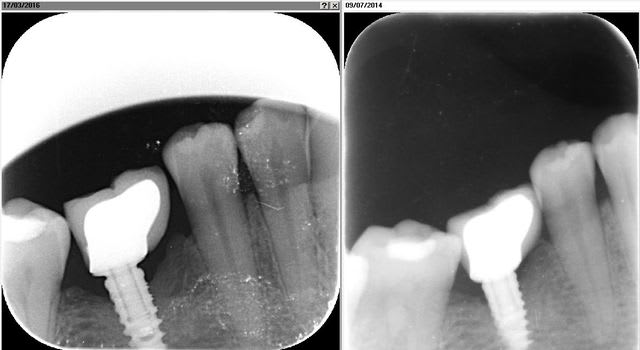

Pour illustrer, deux radios prises il y a deux jours sur deux implants chez la même personne, l'un posé en 2007, l'autre en 2008. Tu vas tout de suite voir la différence à moyen terme et quel sera la différence entre un implant cone morse posée en juxta osseux et en infra osseux.

Radio donc à années+8 ans et +9ans.